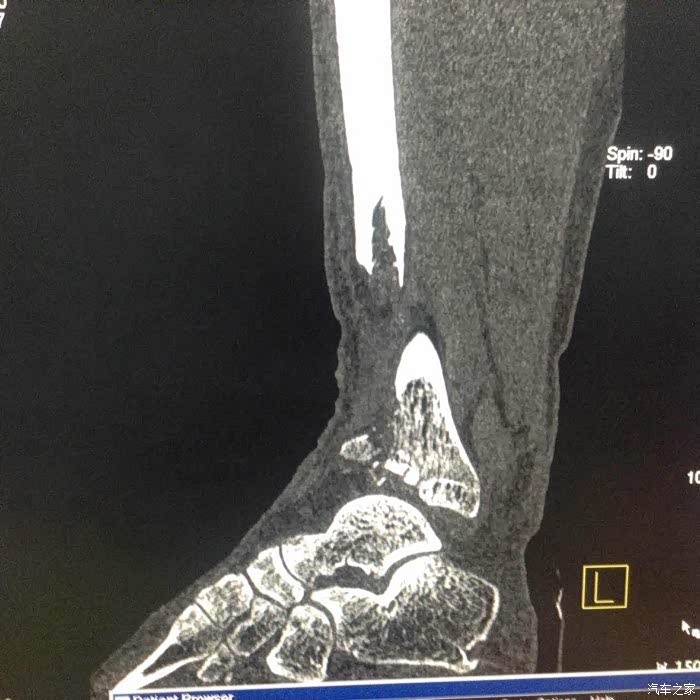

记得当时撞车后,我发现右脚像秤砣一样乱晃,我就明白了,厉害了我的哥。

此时还没有水肿,正在处理伤口看腿型大家可以看得出畸形了。